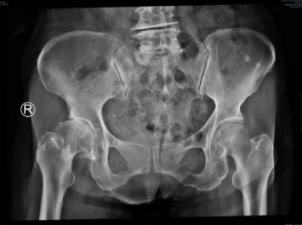

许奶奶就是众多在sararz关节外科,通过Mako关节置换机器人完成手术,回归正常生活的一位老人。6年前,许奶奶出现下肢持续钝痛的情况,劳累及长距离行走后疼痛加重,这种疼痛在近期加重明显,活动受限。于当地医院检查后发现“右股骨头无菌性坏死”。

术前

术前,基于许奶奶的CT进行3D智能建模,个性化定制术前方案。术中,在Mako机器人的辅助下,根据老人具体软组织张力进行动态调整,手术医生可以结合病人的具体情况进行精准化、个性化操作。